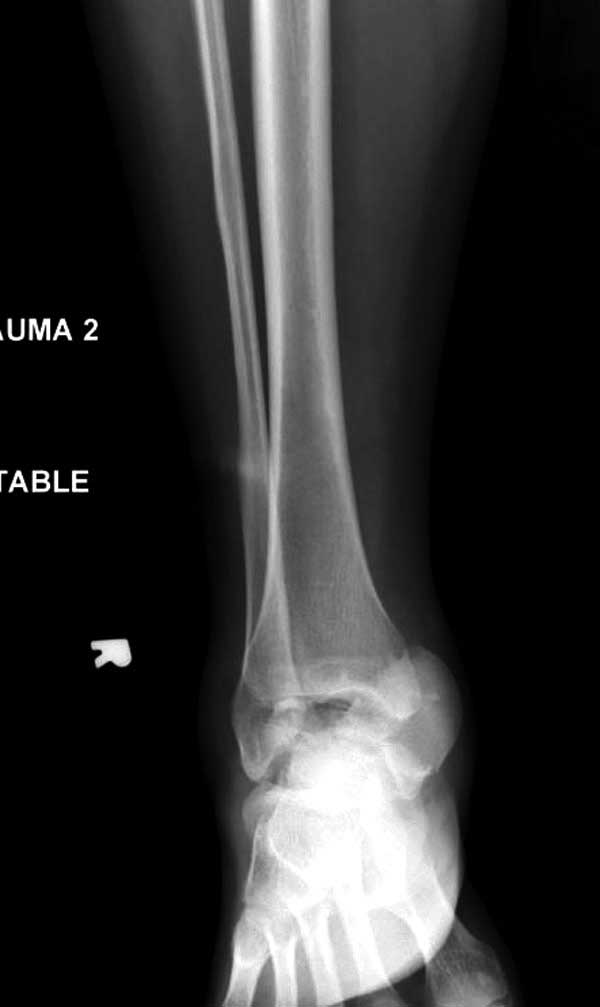

Женщина 28 лет, политравма.

По протоколу обследования больных с травмой сделаны все исследования и выставлен диагноз: разрыв печени и селезенки; множественные переломы ребер и лицевого черепа; стабильный перелом позвоночника, переломо-вывих головки левого бедра, перелом диафиза правого бедра, переломо-вывих правого тарана.